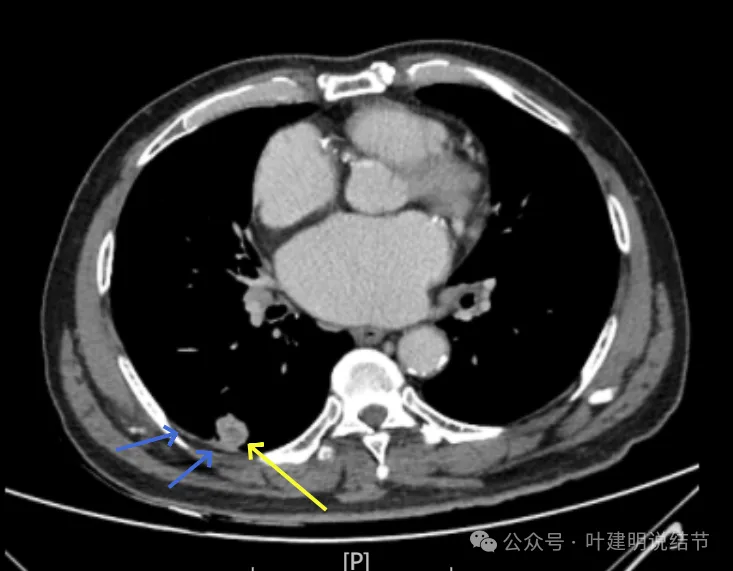

右下新增病灶,混合密度,整体轮廓较清,瘤肺边界欠清。

有小血管进入,边缘毛糙。

局部有毛刺,但不够锐利;病灶感觉有一层晕似的,邻近胸膜下也有淡磨玻璃影。

实性密度为主,周围少许很淡的磨玻璃影。

边缘不平有毛刺,但不锐利;贴着胸膜但无明显牵拉。局部表面有浅分叶似的,但总体膨胀感不够。

病灶表面不光滑,边上有晕,邻近有淡磨,贴着胸膜无牵拉。

病灶边缘欠清晰,瘤肺边界稍模糊。较宽的基底贴着胸膜。

病灶有血管进入,有浅分叶,实性为主,邻近胸膜有片状淡磨玻璃影,近胸膜无牵拉。但有一定膨胀性。

病灶实性,与血管关系较为密切。

血管走向病灶,但似乎没有被病灶影响,有向内侧的分支甚至没有哪怕一点凹向病灶侧。整体显得偏模糊。

边缘区域杂乱,边糊。

增强纵隔窗见病灶内部的密度好像低于周围区域,像坏死。

邻近胸膜无牵拉,灶内有低密度区,局部有点状液性密度。邻近胸膜较为广泛的增厚或胸膜反应。

病灶与胸膜接触面宽,病灶内部密度较低。